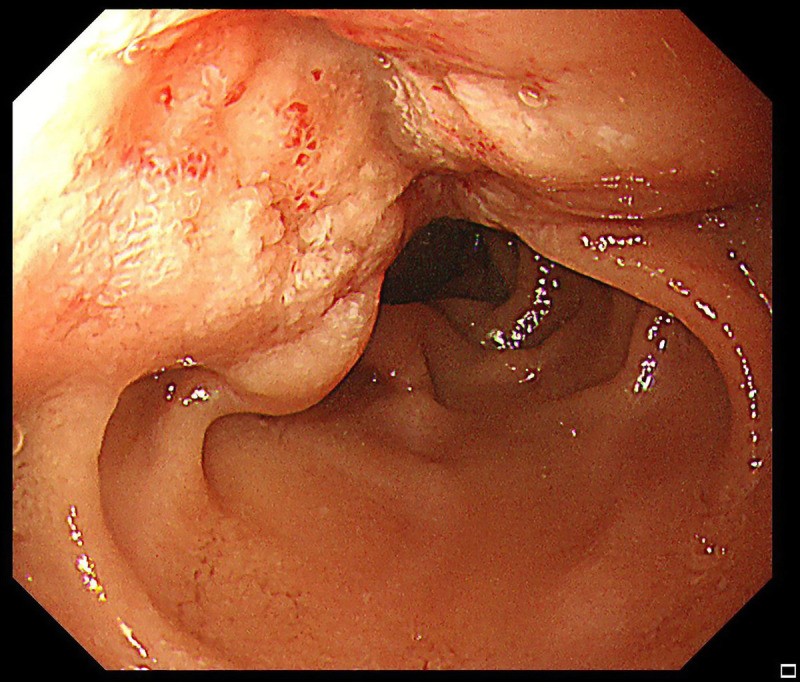

An unusual case of duodenal neuroendocrine tumor presenting with melena diagnosed by EUS-guided fine-needle biopsy.

一例不寻常的十二指肠神经内分泌肿瘤病例,通过胃肠道超声引导下细针活检确诊。